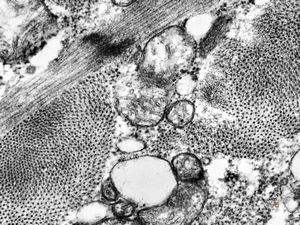

normal cardiomyocyte … transversal section (m … mitochondria, a … actin, my … myosin, arrow … tubules of s